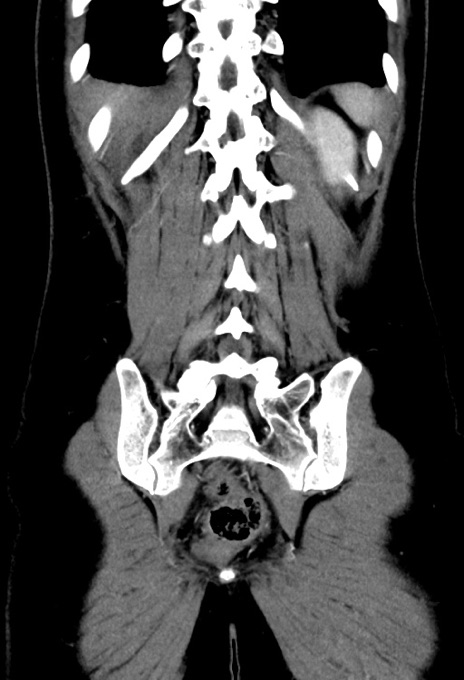

症例17(冠状断像)

【症例】20歳代女性

【主訴】嘔吐、下腹部痛

【現病歴】昨日夕食後に嘔吐し下腹部痛が出現。本日になっても嘔吐持続し改善しないため来院。

【身体所見】意識清明、BT 37.2℃、BP 108/67mmHg、腹部:平坦、やや硬、下腹部正中から右にかけて圧痛あり、反跳痛軽度あり、tapping pain(+)。

【データ】WBC 13600、CRP 14.94